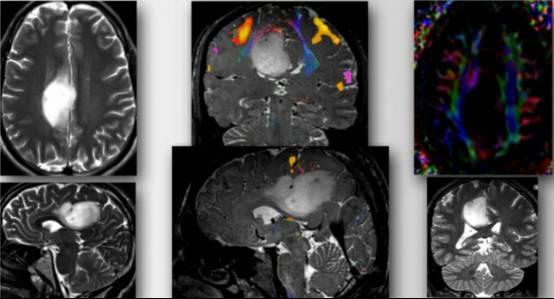

图7. 术前影像学提示为低级别胶质瘤,位于右侧脑室周围并扩展至额叶内侧。中间一列的上图(冠状位)和下图(矢状位)fMRI提示肿瘤位于感觉运动功能区。扩散张量成像(DTI)(右上图)显示肿瘤推挤运动功能纤维束移位。

为了避免过度牵拉同侧功能区,到达肿瘤外侧缘,笔者使用经对侧纵裂入路切开大脑镰技术安全切除肿瘤。

图8. 经大脑镰入路手术角度(最上图)。笔者使用脑皮层刺激定位额叶内侧至肿瘤前部功能区。使用皮层下功能区定位和经大脑镰“斜线”入路切除肿瘤。术后影像提示占位完全切除(底下图)。